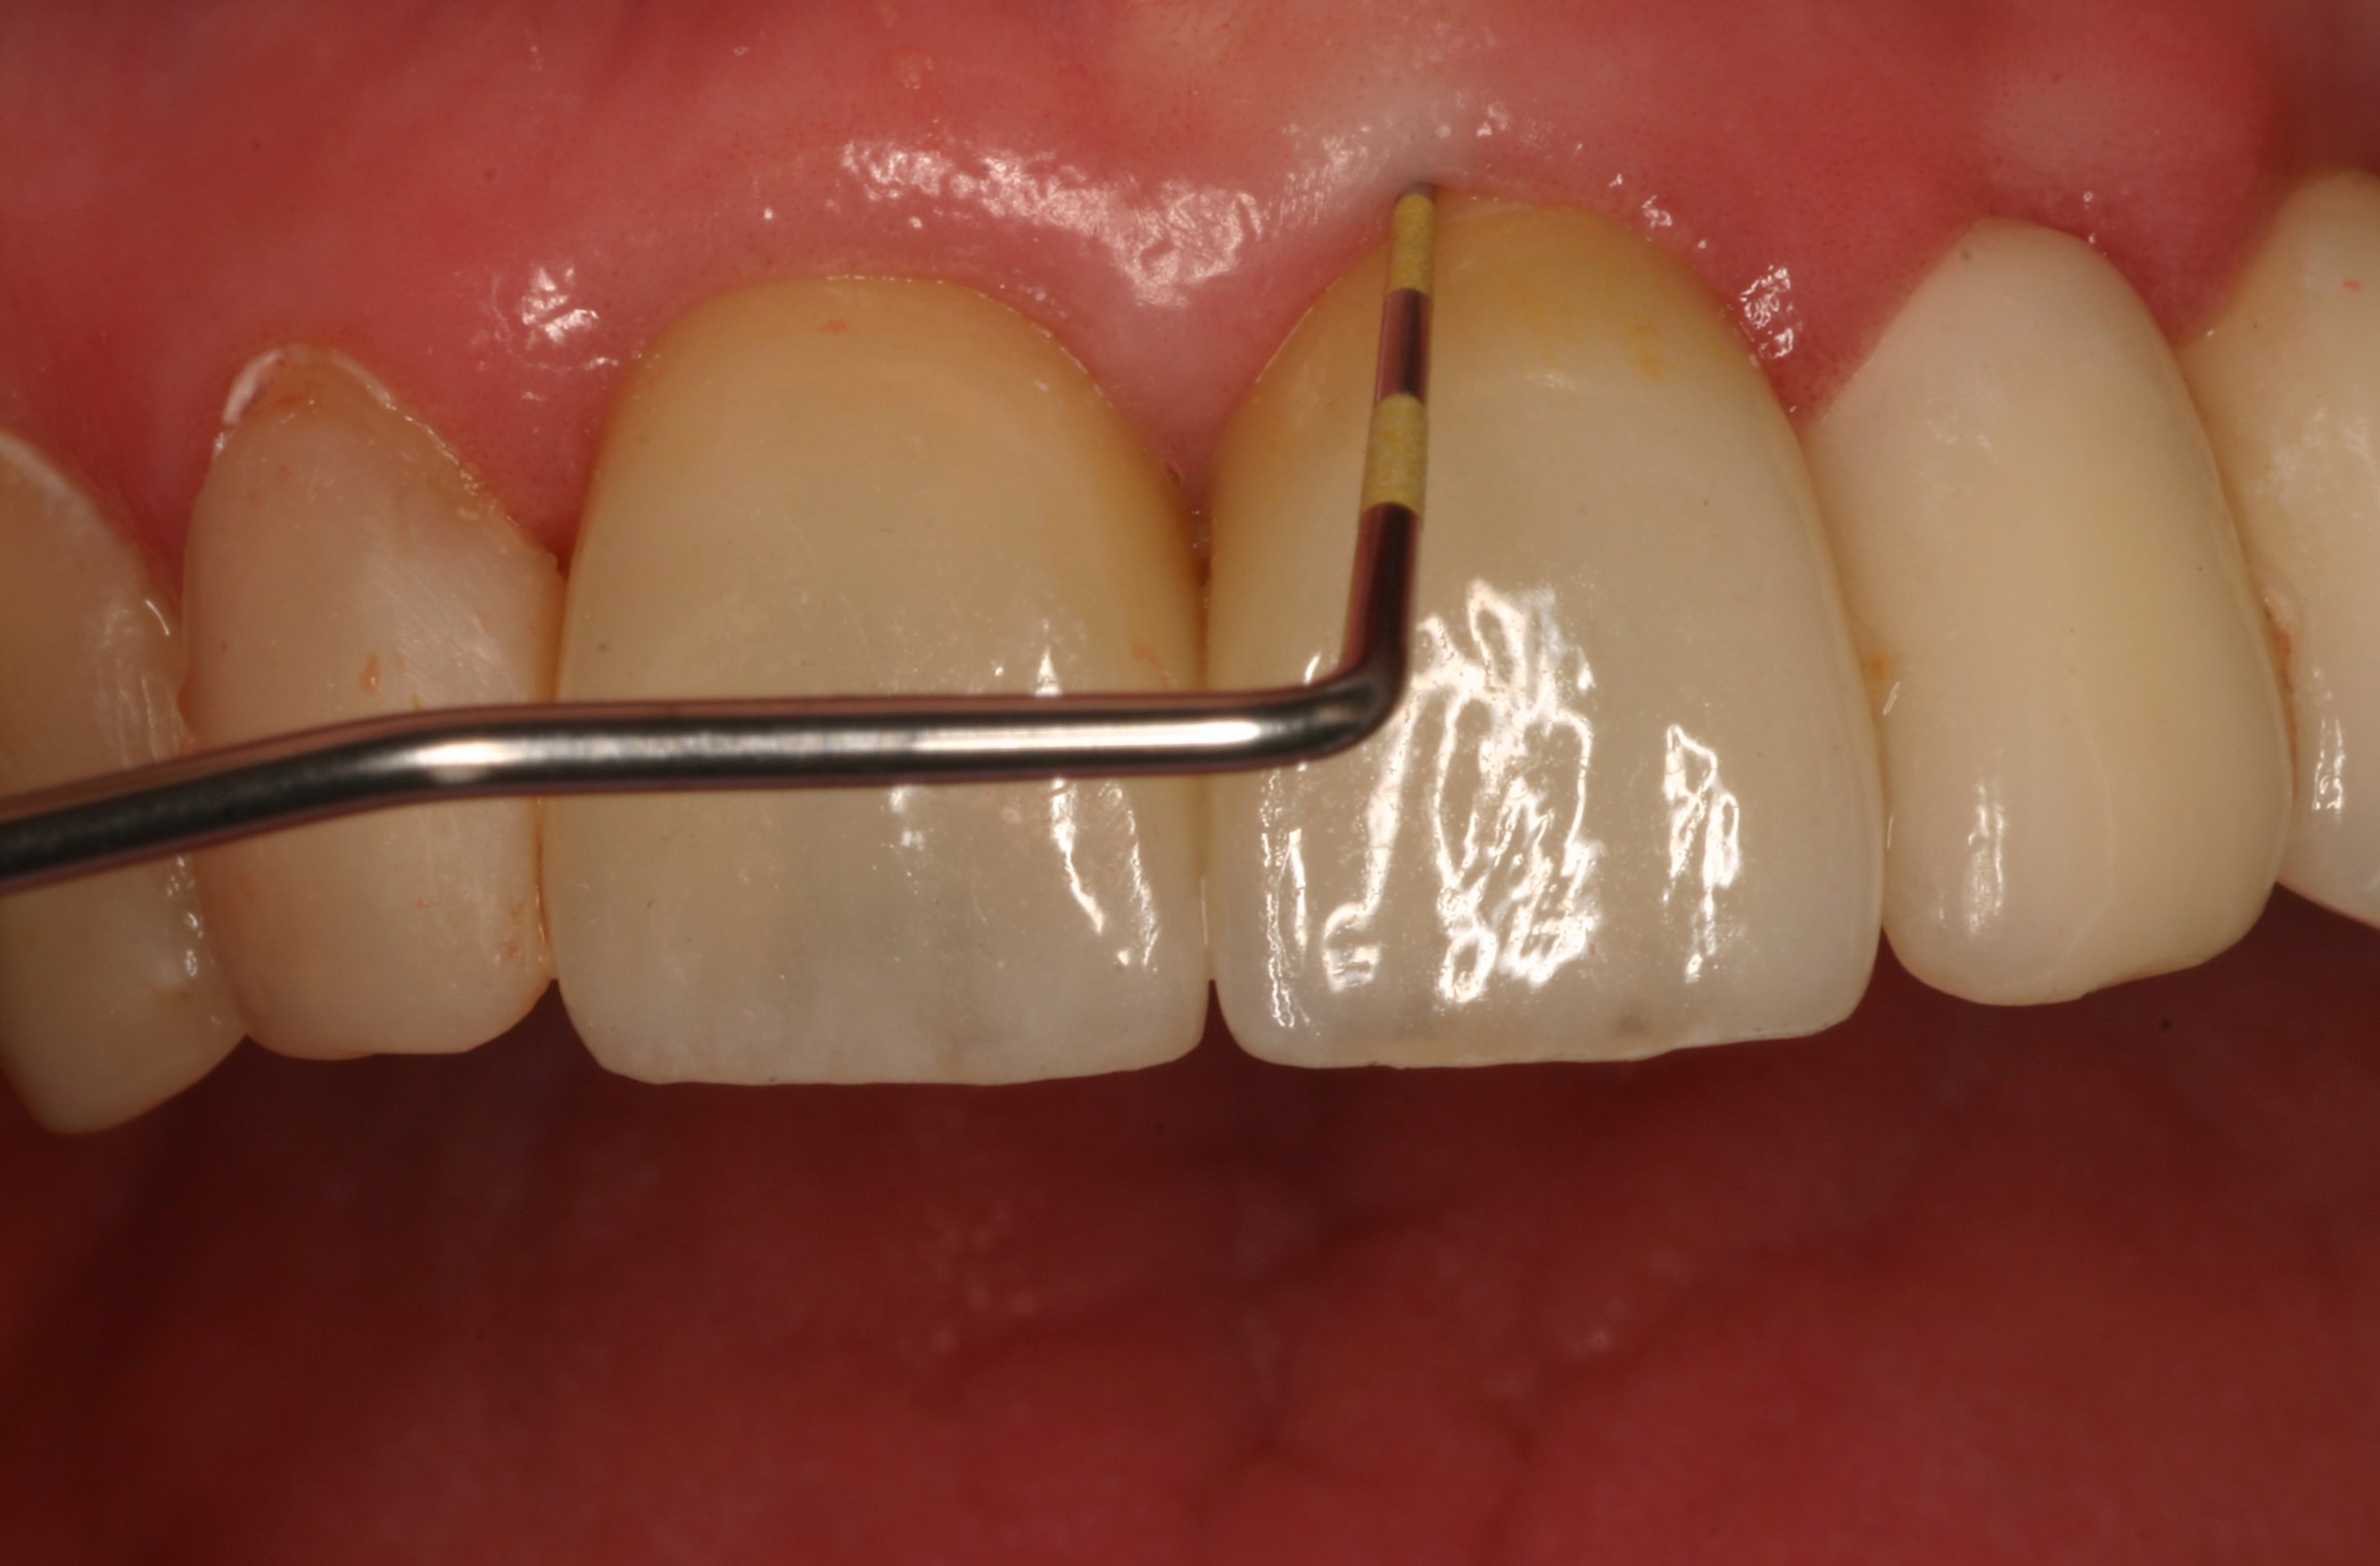

The final impression (closed tray) was obtained in April 2012. The final ceramic crowns (IPS e.max Ceram) and custom porcelain-veneered, regular-diameter (RD) UCLA abutments (Genesis; and Creation CC, Jensen Dental, www.jensendental.com) (Figure 24, shown with PFM crowns and retention screws) were delivered in May 2012. Using a platform-switched connection, the abutments were torqued to 30 Ncm, the access holes sealed with Teflon, and the final crowns cemented with RelyX Unicem. Figure 25 through Figure 28 show the final IPS e.max Ceram crowns from periapical, facial, and incisal views, with a midfacial PD of 3 mm at the 18-month follow-up (Visit 7). A thick biotype is evident in Figure 26, as determined by the inability to detect the outline of the periodontal probe inserted below the restoration’s gingival margin.50 This image also demonstrates an excellent esthetic outcome.

Although Case 3 showed an 18-month PD of 3.5 mm on the facial aspect of implant position No. 9 (the greatest PD recorded at this timepoint), good gingival tone and excellent esthetics were also evident at this visit (Figure 26).